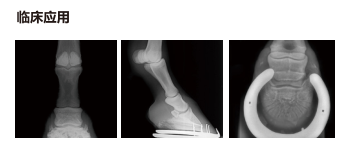

兽用x射线解决方案